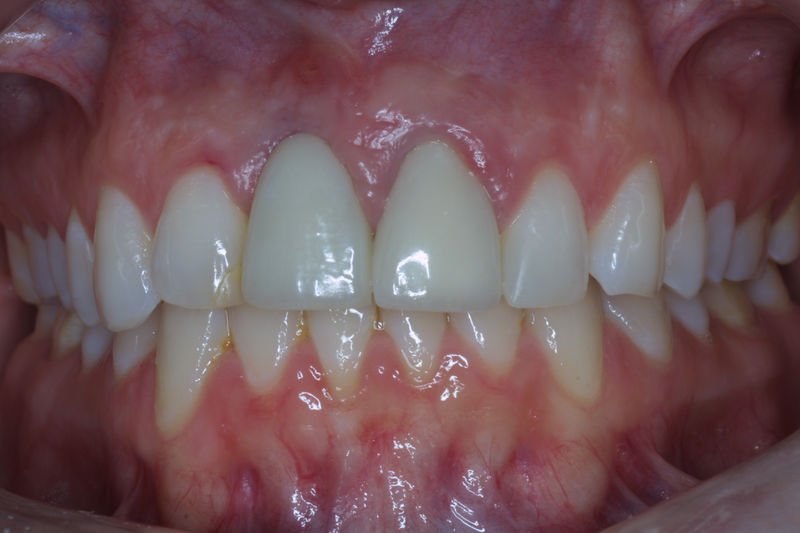

Implante fracasado, extracción, carillas, coronas y prótesis fija.